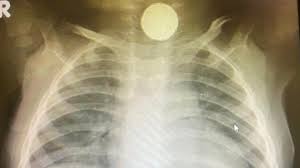

Afortunadamente, la mayoría de los cuerpos extraños suelen llegar al estómago y luego eliminarse. Algunas veces estos objetos pueden hacerse visibles por medio de radiografías, dependiendo de la radio opacidad de los mismos, (monedas, medallas, etc.).

Es evidente que una aguja o un alfiler de gancho abierto tendrá más posibilidades de impactación que objetos redondeados. Sin embargo, hay algunos que, dada su composición pueden lesionar en forma seria cualquier sector del organismo donde se alojen. Estos fenómenos suelen ser ocasionados por las pilas o baterías, en especial las de litio, vulgarmente conocidas como de “botón” por su forma característica.

La ingesta de una pila botón y su impactación en cualquier sector se asocia con un riesgo de sufrir graves lesiones y, en algunos casos, la muerte, particularmente en niños más pequeños.

La impactación de una pila botón resulta en daño eléctrico, mecánico y cáustico en la mucosa esofágica subyacente. La consecuencia, si no se la extrae en forma rápida, es la necrosis del sector donde ella ocurre y luego la perforación, con la gravedad que de ello se desprende.